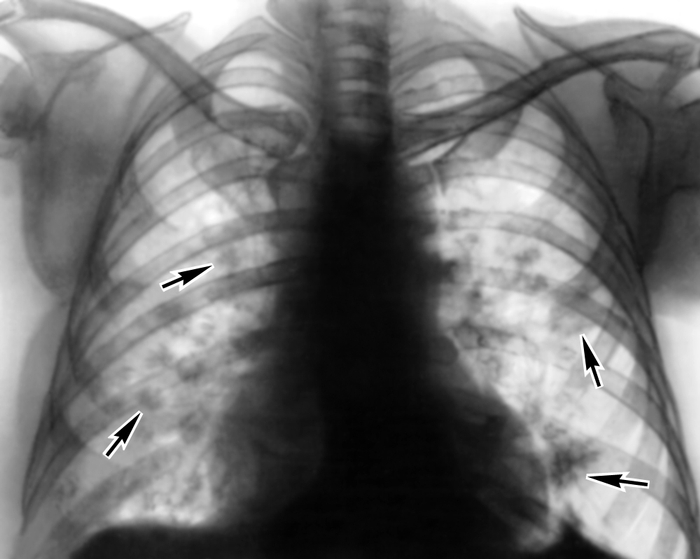

Медицинская тема: легочные осложнения при пневмонии